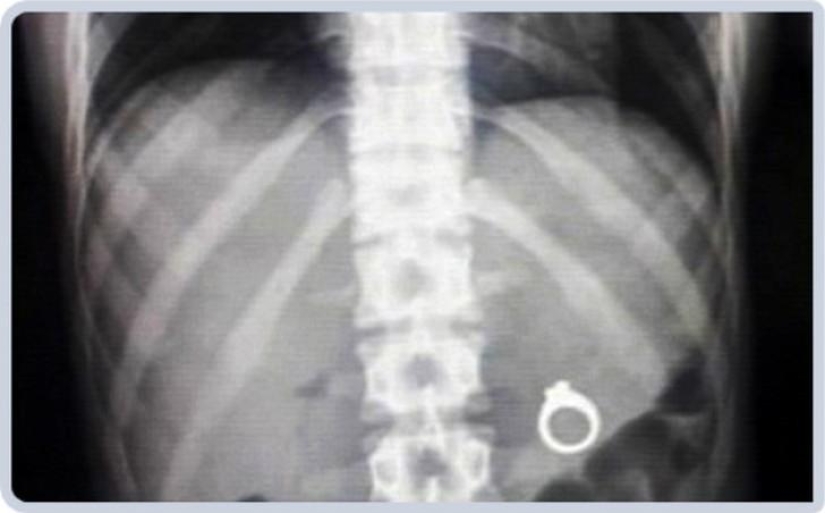

Anillo de bodas.